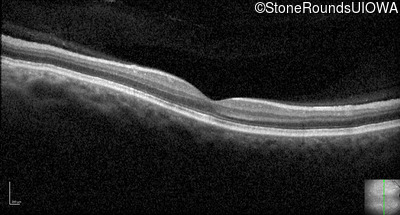

Optical Coherence Tomography - Right - 20/160 -1

Exemplar / OCT Stack